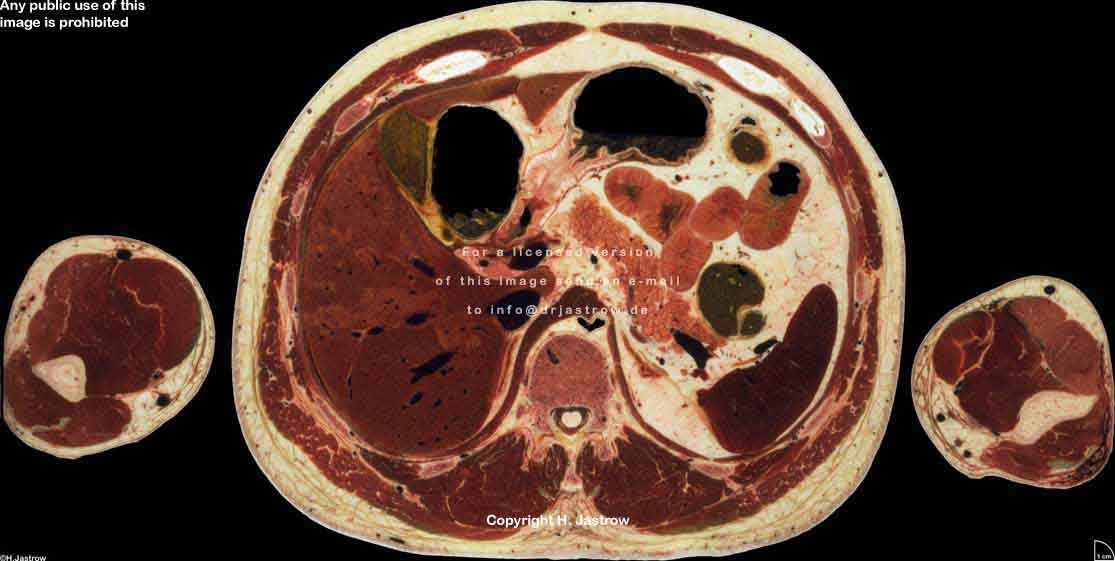

Visible Human male: Sectio transversalis 1558

CT

NMR

Pd                          / T2 \                         T1